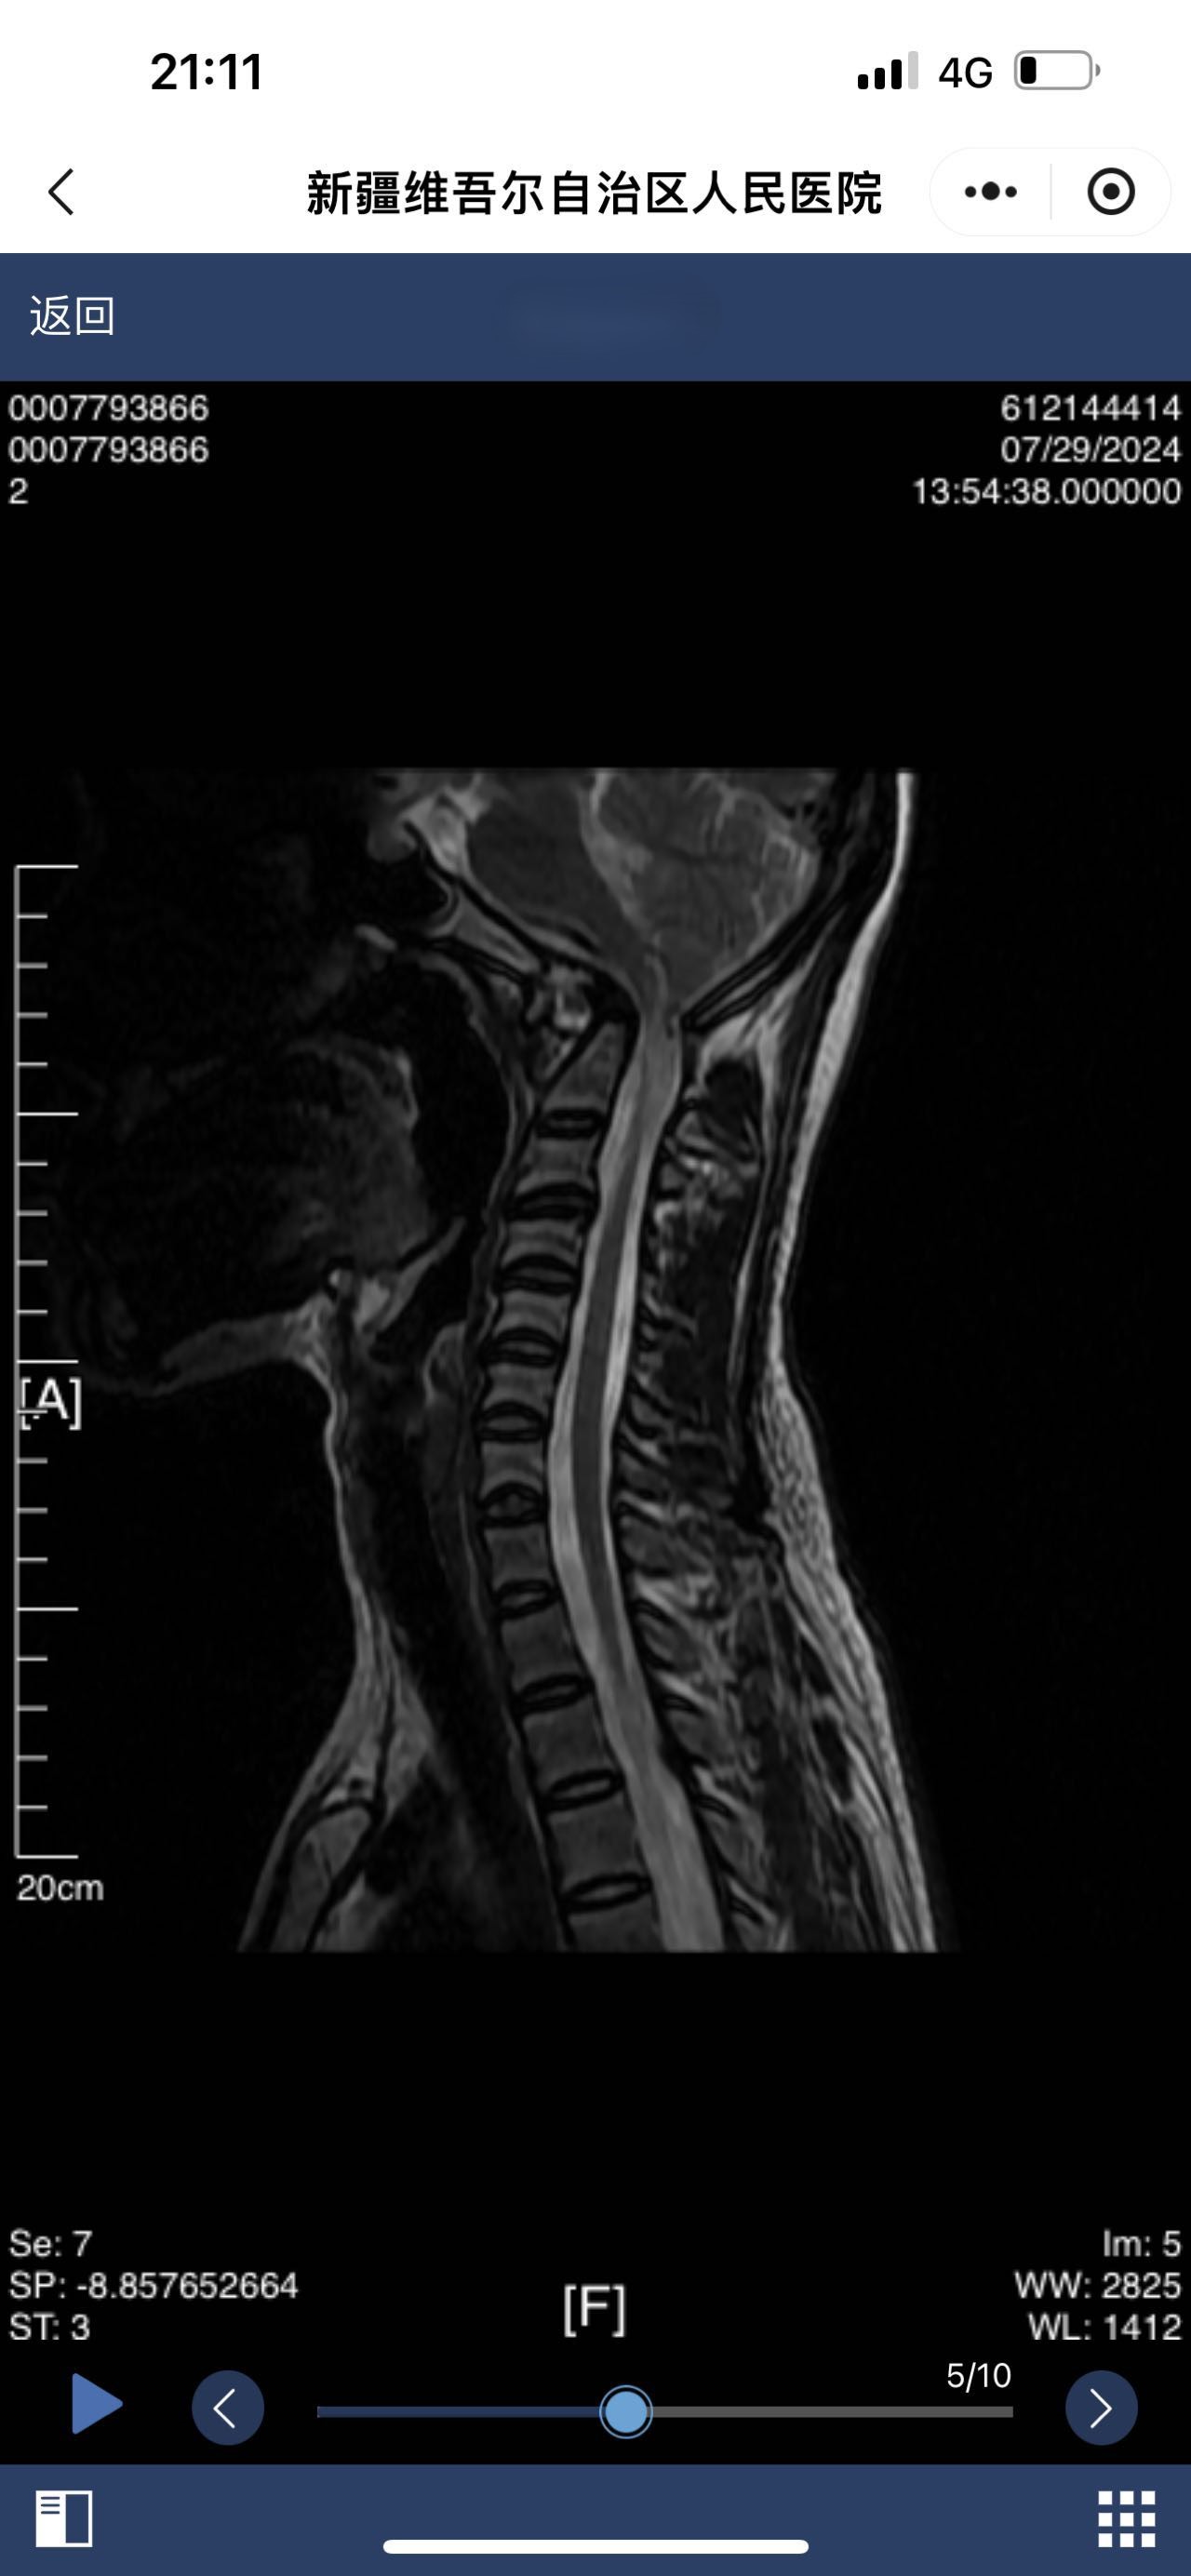

• 诊断:颅底凹陷

• 影像:

• 术后影像: